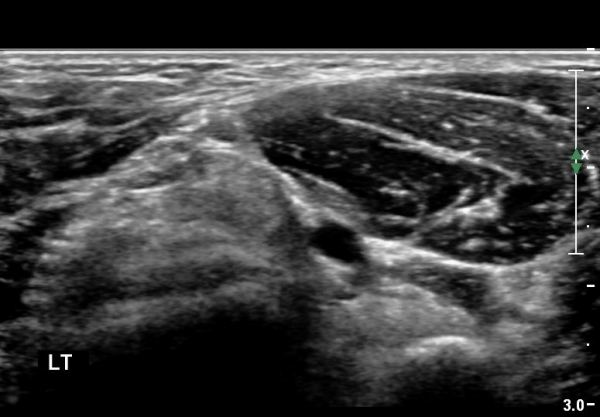

ŽÃËÀÚ¸¦ Á¶±Ý ¸»´ÜÀ¸·Î À̵¿Çϰí ŽÃËÀÚ¸¦ ¸Ó¸®ÂÊÀ¸·Î ±â¿ïÀÌ´Ï À̵ιڱٰÇÀÌ ¶Ñ·ÈÇÏ°Ô °üÂûµÇ´Âµ¥ À̵ιڱٰÇÀÇ ºÎÁ¾ÀÌ °üÂûµÊ(±×¸² 3).